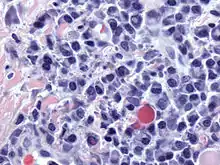

![]() Micrograph of malignant plasma cells (plasmacytoma), many displaying characteristic "clockface nuclei", also seen in normal plasma cells. H&E stain. | |

Plasma cells are large lymphocytes with abundant cytoplasm and a characteristic appearance on light microscopy. They have basophilic cytoplasm and an eccentric nucleus with heterochromatin in a characteristic cartwheel or clock face arrangement. Their cytoplasm also contains a pale zone that on electron microscopy contains an extensive Golgi apparatus and centrioles . Abundant rough endoplasmic reticulum combined with a well-developed Golgi apparatus makes plasma cells well-suited for secreting immunoglobulins.[4] Other organelles in a plasma cell include ribosomes, lysosomes, mitochondria, and the plasma membrane.

Plasmacytoma, multiple myeloma, Waldenström macroglobulinemia, heavy chain disease, and plasma cell leukemia are cancers of the plasma cells.[33] Multiple myeloma is frequently identified because malignant plasma cells continue producing an antibody, which can be detected as a paraprotein.